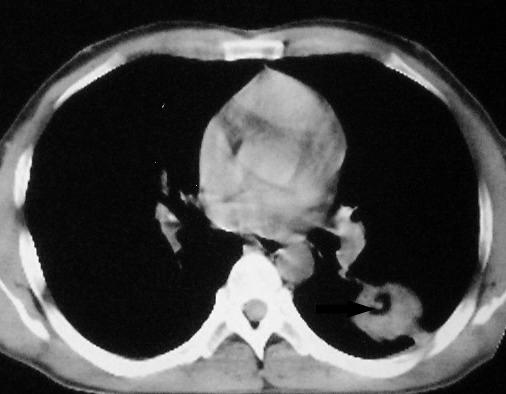

m      37y      发热   咳脓痰月余      ct肺脓肿但住院抗炎治疗后双肺内结节不知该如何解释

治疗后见左肺下野病灶较前缩小但双肺内结节影似无变化请较各位老师该如何下结论    治疗前wbc14.5 治疗后wbc 11.0

如果你仔细的同层面对比,你会发现所有的病灶均有比较明显的吸收、缩小。病变的形态,特别是脓肿的形态、壁的厚薄、内壁均有很大的变化,均在往好的方面发展。与临床症状、血像均符合,治疗效果比较显著,就是肺脓肿并双肺的化脓性炎症灶。